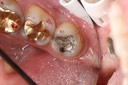

Photos of Clinical Operations

Mentors: Drs. Randy Allan, Greg Card, Peter Kearney

Clubs #44 and #50 joint meeting